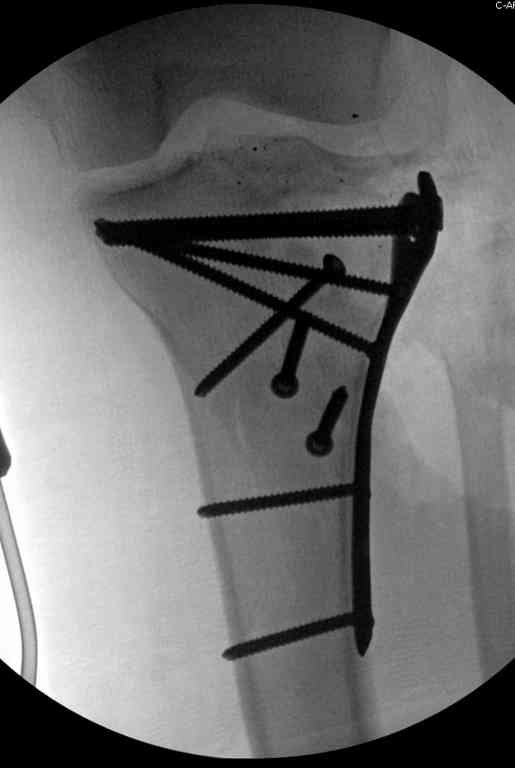

Поступила к нам пациентка 19 лет с диагнозом "Состояние после открытого многооскольчатого перелома дистального метаэпифиза правого бедра, проксимального метаэпифиза большеберцовой кости". Травма в июне 2010 года в Индии. ДТП.

Тамошние доктора выполнили ПХО с удалением фрагментов латерального мыщелка бедра. Наложен АВФ. По возвращению в Украину через 1,5 месяца АВФ демонтирован. И так как смещение фрагментов бедра не устранено, было принято решение после заживление ран от стержней выполнить МОС. Не сколько для четкой анатомической репозиции сколько для подготовки к установке эндопротеза в будущем. Что и было выполнено 10 августа. Интраоперационная картина следующая. Дефицит практически всего латерального мыщелка бедра. Была выполнена попытка закрепить то что осталось от мыщелка, но он развалился на фрагменты. ВЫполнен ситуационный синтез спицами. Дефект заполнили бикортикальным трансплантатом из крыла подвздошной кости, МОС страйкеровским фиксатором. В послеоперационном периоде к 10 дню начались боли, гипертермия. Повышение СОЭ, лейкоцитоз. Посев крови транзиторная бактериемия золотистого стаф. Взяли в операционную. Выполнили дренирование сустава и области п\о раны. Получили гематому фактически с гноем. Температура нормализовалась. Назначили ванкомицин по 1000 мг 2 раза в день.который принимает с 28 августа по сей день. Температура нормальная, СОЭ на убыль. Посевы отделяемого стафилококк 2 ст активности. Но отделяемое по дренажам продолжает идти в достаточном количестве. Взял посев, сеется стаф. 3 ст активноси. К ванкомицину, понятно, слабочувствителен. Что в этой ситуации посоветуете?

Коллеги фиксатор Numelock II

На вашем снимке из-за ротации трудно угадать положение пластины, и желательно сделать снимок с захватом верхнего участка бедра.

Одинокий кортикальный шуруп не удержит тибиальный бугор, сустав тибиал плато оставлен без репозиции и фиксации.